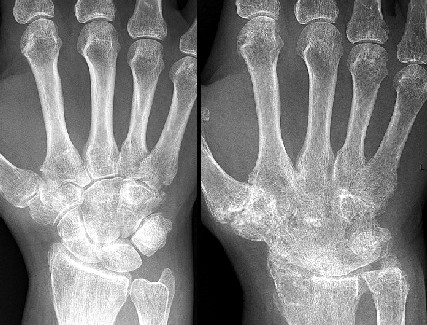

Photo: Mikael Häggström - Anklyosis in the Hand: Normal (left), Fused (right)

For ankle dislocations, Atkins also notes that some patients have trouble with anklyosis, which refers to fusion of the bones in a joint. Atkins says that this is a problem particularly for older patients and warns "when we lend a helping Hand, and fix it immoveably, as it were, by Bandage and Splints, we have Reason to fear an Anchilosis by it"6. He goes on to explain "The Synovia [synovial fluid] in the Joints, by so long a Stillness and Inaction, both here [in a fracture] and in the Luxation, (curved or strait) gluing the Heads of the Bones like a Callus. I have seen the Tibia and Femur, the Humerus, Ulna and Radius, from such a Cause, so cemented, as to appear like one continued Bone."7However, he has no suggestions for remedying this.